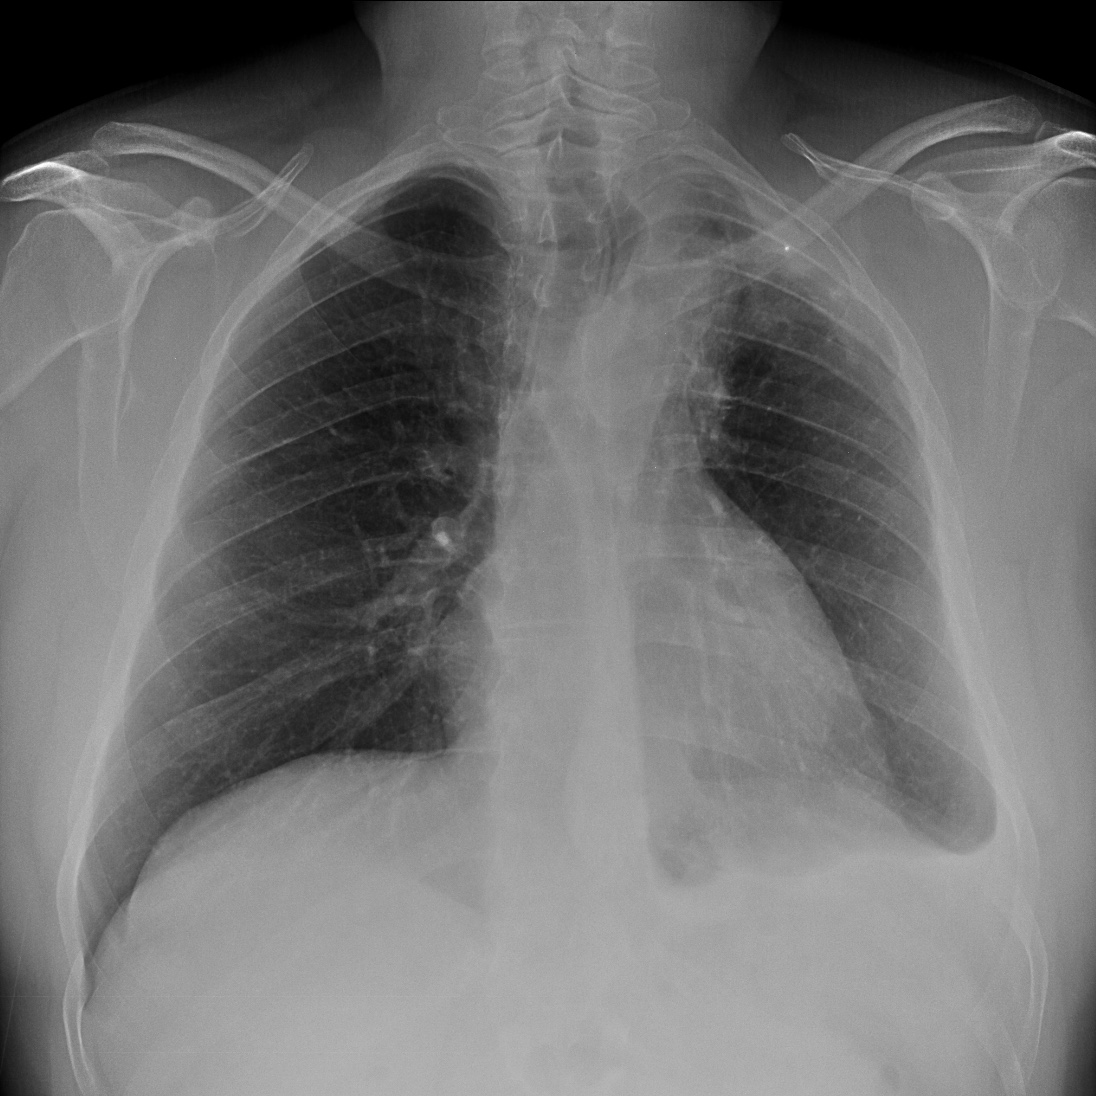

Solución: Es un estudio Normal. Silueta cardiomediastínica y parénquimas pulmonares sin alteraciones significativas.